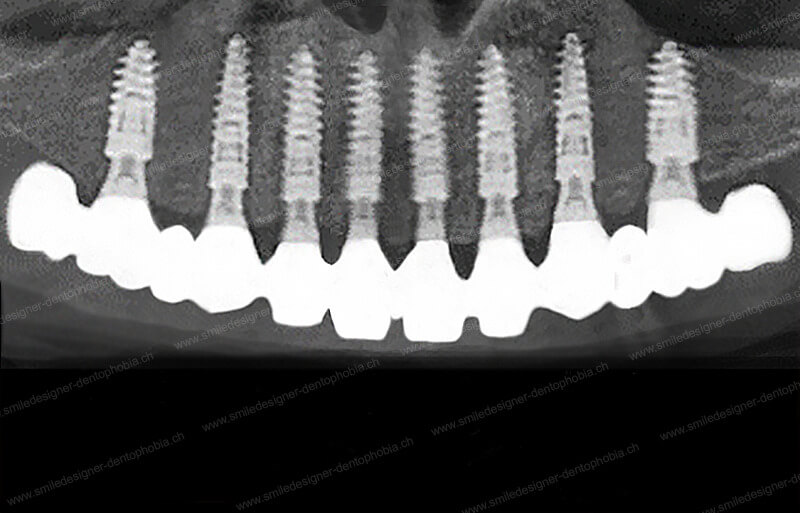

Cas clinique « DAMAGE CONTROL MCI » maxillaire : Bridge implanto-porté avec extensions postérieures (ALL ON 8). Version définitive des bridges avec un cosmétique en céramique.

- 8 implants au maxillaire et 6 à 8 implants à la mandibule sont posés en une seule séance, sous anesthésie générale.

- Bridges provisoires en composite sont fixés dès les premiers jours, suivis de prothèses définitives en céramique après 6 à 12 mois de cicatrisation.

- Extensions postérieures (prémolaires/molaires) permettent de restaurer une fonction masticatoire minimale et un calage articulaire, même en cas de résorption osseuse importante.